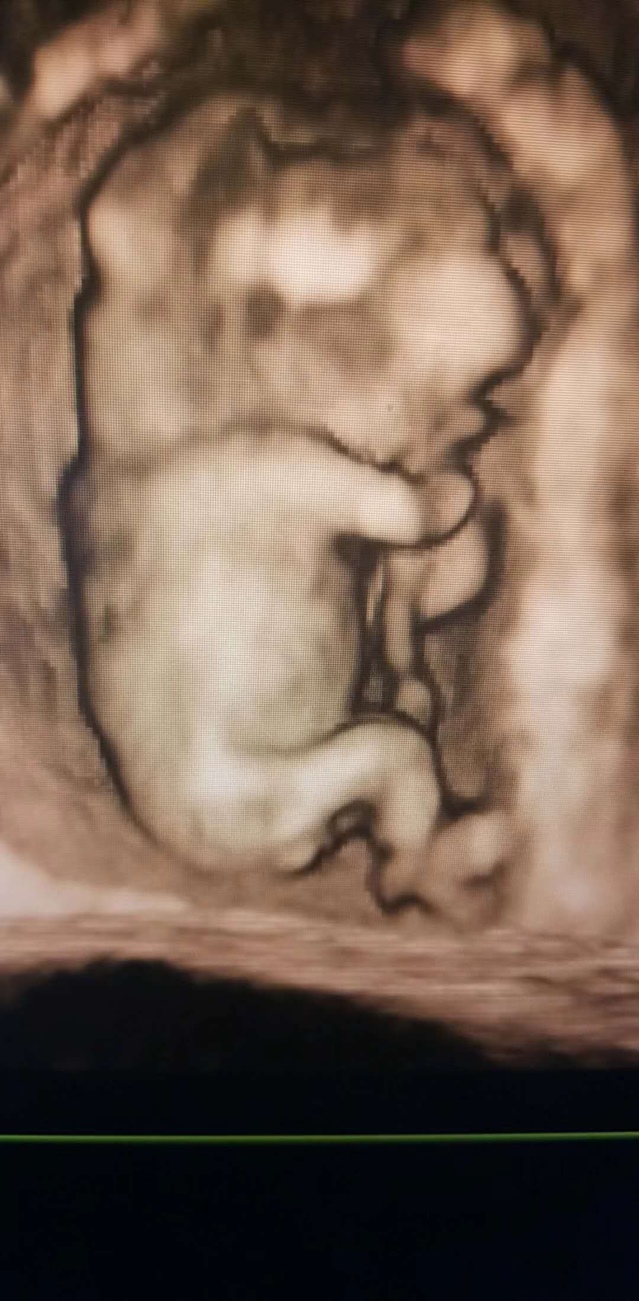

孕13周+0天

四个月才分性别,这个时候男女特征是一样的,看不出来的

好像看见蛋蛋了。

女宝宝阴部发育初期也是鼓鼓囊囊的。要中晚期才看的准。

感觉是儿子,中间一坨肉肉

男孩女孩在没发育完全的时候,有时候有点凸的,还不能判断,可以去优酷看下子宫日记